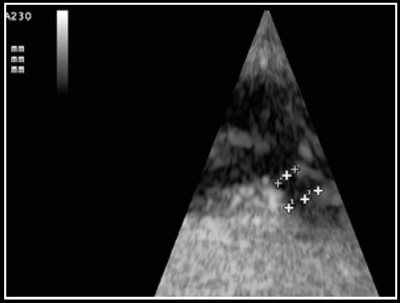

Photo 5 - Mesure des trois principales dimesions du canal artériel : largeur à la naissance et à l’abouchement, longueur.

La mesure de la taille du canal est réalisée en mode bidimensionnel ou en mode Doppler couleur, après identification. Les deux modes de mesures sont valables, la mesure en mode bidimensionnel étant la plus précise.

La mesure concerne la longueur du canal, la largeur à sa naissance sur l’aorte, et la largeur à son abouchement au niveau du tronc pulmonaire (Photo 5) [2].